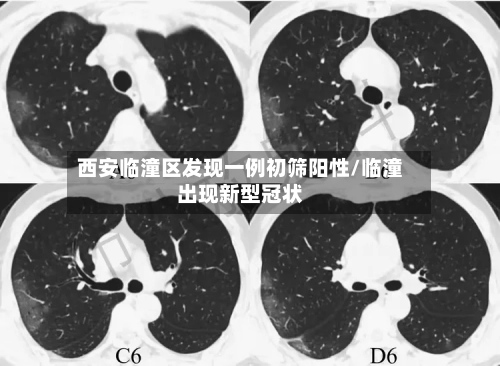

西安临潼区发现一例初筛阳性/临潼出现新型冠状

西安有多少粒〖壹〗、例如,2024年4月4日,西安市花粉浓度曾达到4690粒/1000平方毫米,过敏风险等级极高,提示春季树木花粉的致敏风险不容忽视。花粉浓度预测与影响花粉浓度受季节和天气共同影响。秋季天气转凉时,蒿草花粉浓度反而上升;春...